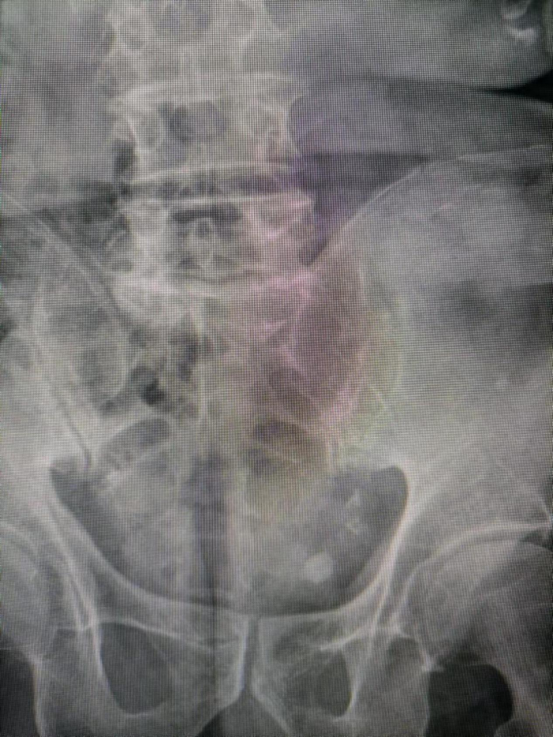

近日,商城县人民医院泌尿外科碎石科完成全面升级!将原有先进的单定位“体外冲击波碎石机”,升级为X光和超声双定位碎石机,使得碎石治疗定位更加精准,有效率达到98%以上,并且,扩大了尿路结石可碎石治疗的范围,用郑州大学第二附属医院王友志教授的话:实现了泌尿系结石碎石治疗无死角! 随着碎石科门诊设备升级改造完成,立马迎来了来自郑州和漯河的两位输尿管结石急性梗阻高危患者,其中一名放有颅内支架、另一名患有药物性肝炎。经长期驻扎帮扶我院有着丰富碎石经验的王友志教授详细评估后,于当日下午为两名患者顺利完成碎石术,不到半小时即缓解了患者的疼痛,效果非常显著。随后,又迎来来自山东的巨大膀胱结石患者,碎石科彭仁焕主任为患者细致的检查后,由他亲自操作,经过30分钟碎石治疗,患者自解小便立即就看到了排出的碎石屑。慕名远道而来的患者们都连连感叹来商医看病虽然路途有点远,但安全有效且经济实惠! 商城县人民医院泌尿外科碎石科门诊位于门诊二楼东,近期刚完成全面设备升级,拥有先进的超声和X 线双精准定位“体外冲击波碎石机”,可全面开展体外冲击波碎石术(ESWL)。体外冲击波碎石术(ESWL),即俗称体外碎石,是通过超声或 X 线将结石精准定位于体外产生的高能冲击波聚集处,冲击波通过介质传导聚焦,反复作用于体内尿结石的所在部位,从而将结石粉碎,继而随尿液排出体外的治疗方法。具有操作简单、疗效显著、损伤较轻、并发症少、安全性高、费用少的特点,是目前大多数尿路结石急症的首选处理措施。 泌尿结石是泌尿外科常见病,结石可见于肾、输尿管、膀胱及尿路等,结石所在部位不同,表现症状程度不同,发病机制较复杂,病情加重引起肾积水,尿路梗阻等,甚至危及生命。门急诊患者常常以尿痛、血尿、绞痛为主要表现,发病急骤,患者痛苦大。及时排出结石,解除输尿管梗阻是缓解患者症状的关键。 近年来,在院党委的高度重视下,我院泌尿外科紧锣密鼓的开展专科特色业务,而此次顺利开展的体外冲击波碎石术专科业务则为泌尿学科发展又开启了新的征程,为广大结石患者带来福音。下一步我院泌尿外科将一如既往开拓进取,致力于为广大患者提供更好的诊疗服务,在原有基础上锐意创新,不断在泌尿外科疾病的现代治疗领域取得新突破,谱写为群众办好事、办实事的新篇章,为大别山的医疗健康事业贡献力量。 健康就诊地址:门诊二楼东 健康咨询电话:0376——7973081